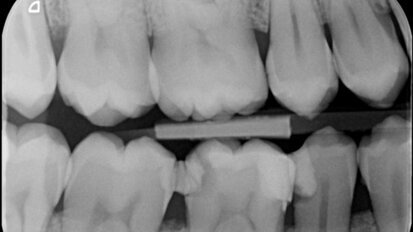

Onderscheid cariës en caviteiten

Eén van de drie voorbehouden handelingen die de mondhygiënist – in een experimenteerfase – zelfstandig mag gaan uitvoeren, is het behandelen van ...